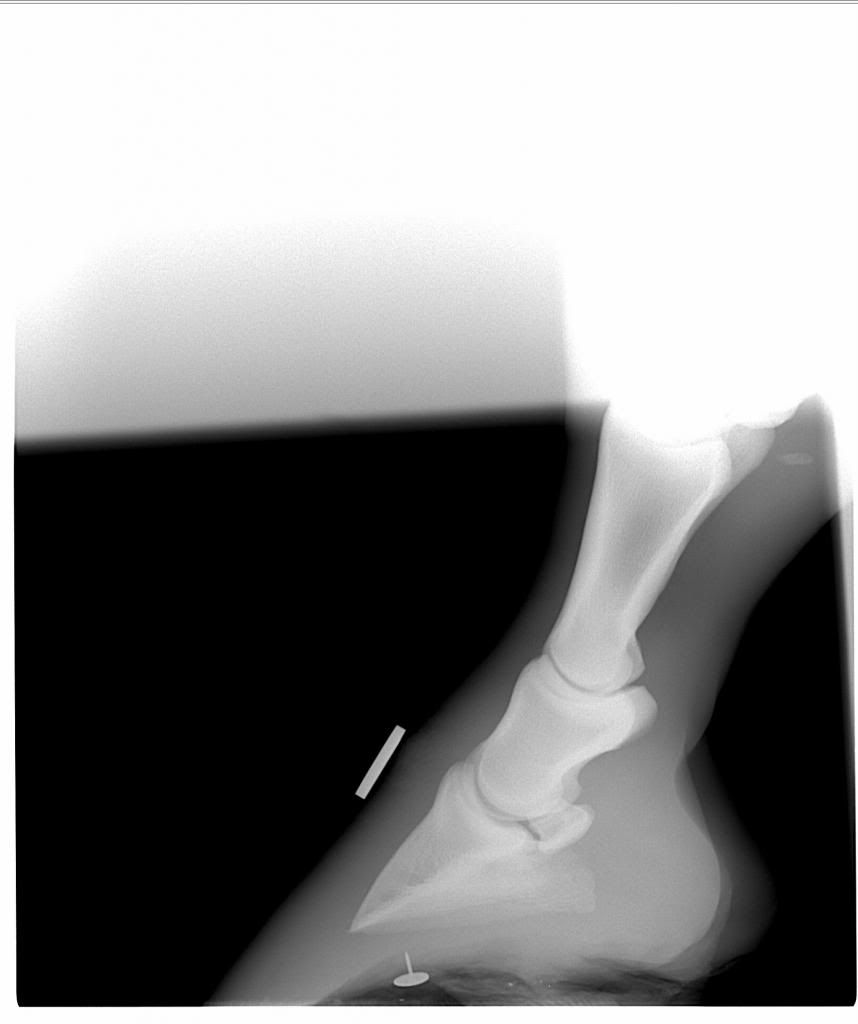

Just out of interest, I have a set of X rays taken of my horse's feet from around 2 years ago, after she had had laminitis.

Even though she was barefoot, I didn't really pay much attention to the feet side of things and left it to my farrier/vet at the time, therefore I don't feel as though I learned anything from the experience and would really value you barefooters comments on what you can see. Now I am very interested in this subject!

As I mentioned, these are not current, they are two years old and my horse was trimmed accordingly, but I would love to hear your thoughts and opinions and anything you can gleam from them, if only as a learning exercise.

Left Hind

The fore hooves are very, very long in the toe. She would have had very stretched white lines. Even on the x-rays you can see the angle that the hoof should have been (under the coronet). If you take that angle down, you can see that the hooves would be much smaller, however the pedal bone would still be rotated down.

All FOUR feet are very long in the toe and flat.

I would say that, even without the pedal bone rotation the horse was metabolically compromised and careful attention needed paying to both diet and trimming.

It was certainly an eye opener and from that day onward I became obsessed with her diet, had the farrier out at least every 6 weeks and he trimmed them to help realign the rotation - I was told it was 9 degrees at the time by the vets.